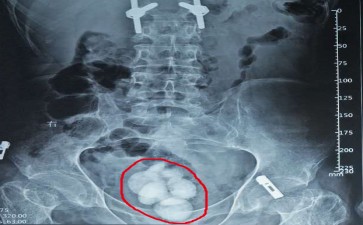

膀胱结石

膀胱结石藏在身体里的小石子会捣乱吗

你是否想过,每天顺畅排尿的背后,膀胱里可能藏着一些“不速之客”——长春结石医院膀胱结石?这些“小石子”虽不起眼,却能搅得你排尿不得安宁,甚至引发更严重的健康问题。

长春结石医院膀胱结石的形成,就像一场“化学实验”的意外。尿液中的矿物质,如钙、草酸、尿酸等,浓度过高时,就会像糖水里的糖分一样,析出结晶。这些结晶逐渐聚集、增大,最终形成结石。而尿路梗阻、膀胱异物、感染、代谢异常等因素,就像给这场“实验”添了把火,加速了结石的形成。比如,前列腺增生导致的排尿不畅,就像给膀胱装了个“阀门”,尿液排不出去,矿物质就容易沉淀成石。

长春结石医院膀胱结石一旦“捣乱”,症状可不少。尿频、尿急、尿痛,就像膀胱在“抗议”;血尿,则是结石划伤膀胱黏膜的“证据”;排尿困难、尿流中断,更是结石堵塞尿道的“杰作”。这些症状不仅影响生活质量,还可能引发膀胱癌等严重后果。

不过,别担心,现代医学有“拆弹”妙招。小的结石,多喝水、多运动,就能让它们“随尿而出”;大的结石,则可以通过经尿道膀胱镜碎石取石术、体外冲击波碎石术等微创手术,轻松“消灭”。当然,预防永远是最好的治疗。保持充足的水分摄入,避免高草酸、高嘌呤食物,及时治疗尿路感染和前列腺增生等疾病,就能让长春结石医院膀胱结石“无机可乘”。

长春结石医院膀胱结石虽恼人,但只要我们了解它、预防它、治疗它,就能让这些“小石子”无处藏身!